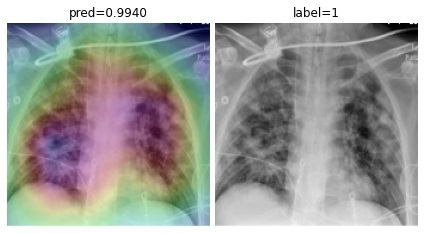

To overcome the aforementioned issues and force the model’s attention to the correct regions of interest (ROIs), we introduce the COVID-CXNet. Our model is initialized with the pretrained weights from CheXNet. A dataset of 3,628 images, 3,200 normal CXRs and 428 COVID-19 CXRs, are divided into 80% as training-set and 20% as test-set. Batch size is set to 16, rather than 32 in previous models, regarding memory constraints. Grad-CAMs of the COVID-CXNet for random images are plotted in Fig. 15.

Refer to caption

Figure 15: Grad-CAM visualization of the proposed model over sample cases

More Grad-CAMs are available in Appendix A. Heatmaps are more accurate than previous models, while an accuracy of 99.04% and an f-score of 0.96 are achieved. Table 3 is the confusion matrix of the proposed model.